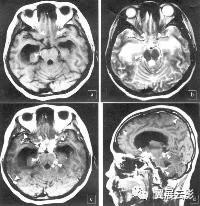

脑膜炎(meningitis)系指软脑膜的弥漫性炎症性改变。由细菌、病毒、真菌、螺旋体、原虫、立克次体、肿瘤与白血病等各种生物性致病因子侵犯软脑膜和脊髓膜引起。

脑膜炎是怎么诊断的?

医生会给你的孩子进行验血或腰椎穿刺以诊断脑膜炎。腰椎穿刺是将一根空心针头插入婴儿的下脊椎,取出脊髓中的液体样本,然后将这种液体送到实验室进行检测。